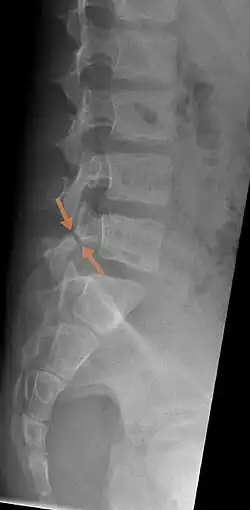

| Arrows show break in pars interarticularis at L5. X-Ray of lumbar spine, lateral projection, in an 11-year-old boy | |

X-Ray

X-rays (electromagnetic radiation) are projected through the body to produce an image of its internal structures. The radiation is more attenuated (absorbed) by the denser tissues of the body (i.e. bone) than the softer tissues (i.e. muscles, organs, etc.) creating a picture composed of shades of grey ranging from white to black. A vertebra with a fracture or defect of the pars interarticularis will have a dark mark through this region of bone. Since this is difficult to see on the AP (anterior posterior) x-ray view an oblique x-ray of the lumbar spine can usually identify the spondylolysis. If inconclusive a further CT scan can produce a 3-dimensional images to more clearly show the defect although the exam increases the patients radiation dose by at least an order of magnitude than plain x-rays.[15][16]